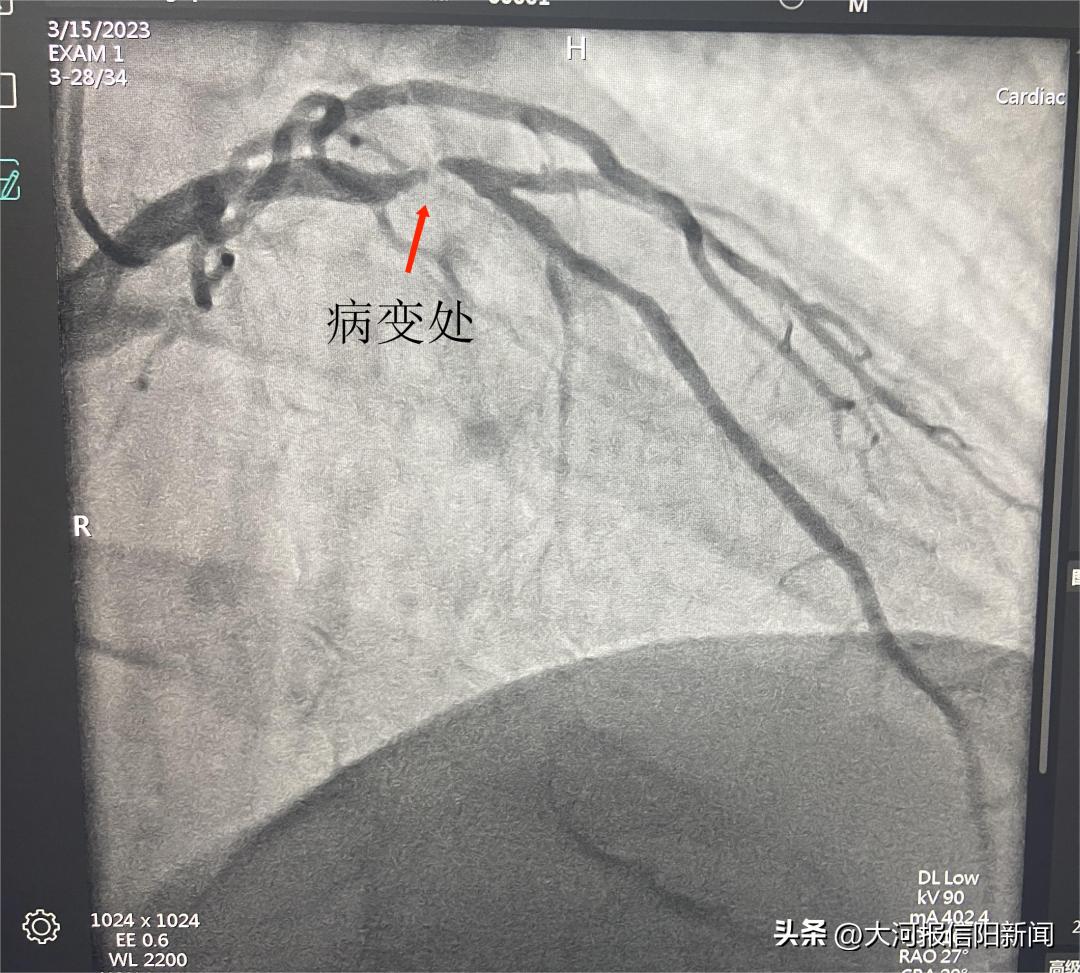

患者陈某,女,65岁,以“间断胸闷气短1月与”来我院就诊,经行冠状动脉造影,提示患者回旋支中段闭塞,术中征得家属同意后,决定开通闭塞血管,经过2个小时不懈努力,终于开通回旋支闭塞血管,术后患者安全返回病房。